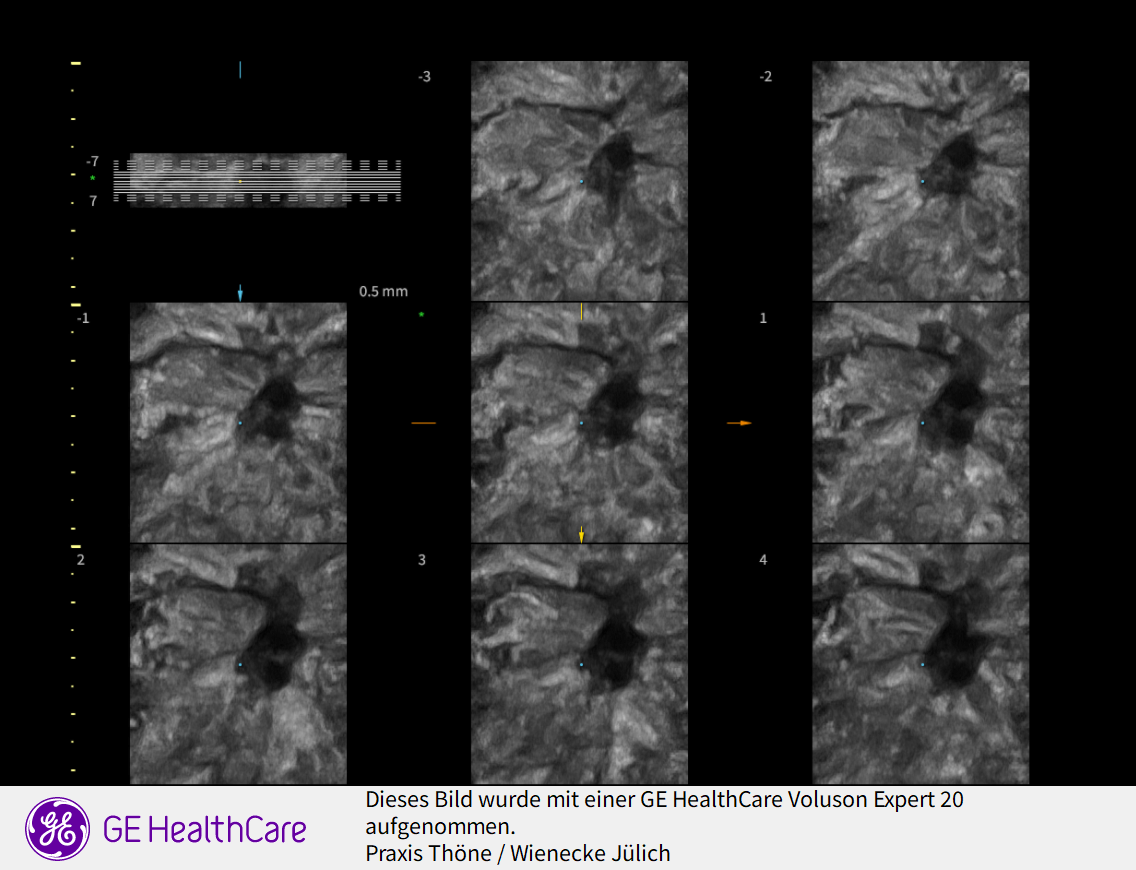

3D Sonographie der Brustdrüse

Was ist der Unterschied zur normalen Sonographie?

Der Ultraschall ist eine Untersuchung ohne Strahlenbelastung. In unsrer Praxis werden hochauflösende Ultraschallköpfe verwendet, die eine hohe Genauigkeit und sehr gute Auflösung ermöglichen. D.h. auch kleinste Veranderungen können schon gesehen werden. Mit der 3 D Sonographie können Veränderungen des Gewebes in ihrer Abgrenzung zum normalen umgebenden Gewebe besser beurteilt werden als nur mit der 2 D Methode. Bösartige Knoten bilden Ausläufer in das umgebende Gewebe, die wie kleine Strahlen einwachsen. Diese Phämomene können mit der 3 D Sonographie beurteilt werden, die Unterscheidung zwischen gutartigen und bösartigen Veränderungen wird genauer und die Rate an unnötigen Biopsien kann vermindert werden.